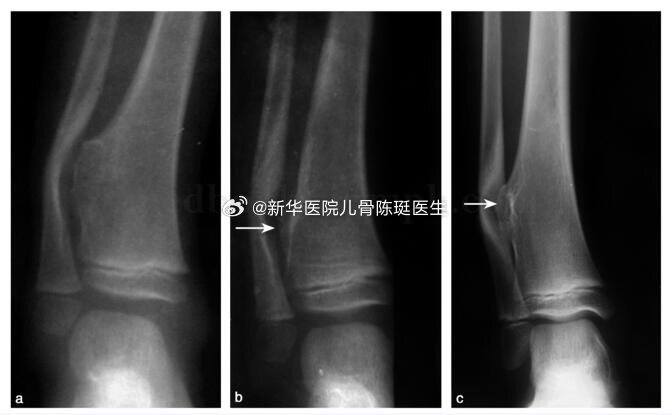

什么是小儿骨软骨瘤?如何治疗!?骨软骨瘤又称外生骨疣,是儿童期最常见的良性骨肿瘤。该肿瘤通常位于干骺端的一侧骨皮质,向骨表面生长。可分为单发和多发性骨软骨瘤。后者有遗传倾向,并影响骨骺发育或产生肢体畸形,称为多发性遗传性骨软骨瘤病,或骨干续连症。本病严格讲来不属于肿瘤,而是生长方面的异常,或称错构瘤。瘤体有软骨帽和一个从骨侧面突出的骨组织。本症又称骨疣,其成因可能是从靠近骨膜的小软骨岛长出,或来自骺板软骨。 凡软骨化骨的部位均可发生,但下肢长管状骨占1/2,股骨下端和胫骨上端最多。其次为肱骨上端,桡骨和胫骨下端以及腓骨的两端。病变位于干骺端,随生长发育逐渐远离骺板。骨疣内的骨髓中脂肪组织丰富。骨疣的增长是靠软骨帽深层的软骨化骨作用。病儿发育成熟后,骨疣即停止生长。成年后,软骨帽逐渐退化以至消失,偶持久存在并可继发为软骨肉瘤。考虑到该肿瘤将随着骺板闭合会停止生长,而且恶变率极低(单发性在0.5%~1%,多发性为2%左右),当出现局部疼痛、妨碍关节活动或压迫血管、神经和脏器时,可以接受手术治疗。

骨软骨瘤病与内生软骨瘤病简介临床上,在所有的良性软骨系统肿瘤中,以骨软骨瘤和内生软骨瘤最为常见。骨软骨瘤和内生软骨瘤多为单发,一旦发病部位达到两处及以上,即可相应诊断为骨软骨瘤病和内生软骨瘤病。这是两种罕见但重要的骨骼疾病,对病人的生活质量和健康状态有着显著的影响,往往在儿童及青少年时期由于骨骼畸形及生长障碍就医而被诊断。成年后,由于关节对位不良,常常导致关节疼痛和退行性变。更为重要的是,尽管两者为良性病变,但均具有恶变为软骨肉瘤的风险。因此,本文将重点介绍这两类疾病的病因、症状、主要治疗方法,以及预防疾病恶变需要注意些什么,供大家学习交流。一、骨软骨瘤病骨软骨瘤病(多发骨软骨瘤),又被称为遗传性多发性外生骨疣(MultipleHereditaryExostoses,MHE),是一种常染色体显性遗传病。它主要表现为多个外生骨疣(即骨软骨瘤)在骨骼表面背向关节生长,这些外生骨疣可以在全身各处出现,但尤其常见于长骨的干骺端,如股骨、胫骨和肱骨,也常见于中轴骨,如骨盆、肩胛骨和脊柱。1.遗传特点骨软骨瘤病的发生与EXT1或EXT2基因的突变有关,约70-94%的多发骨软骨瘤病患者存在EXT1/2胚系突变。EXT1基因在染色体8q24区域,EXT2基因位点在11p11-13,骨软骨瘤病以EXT1突变更为常见。EXT基因编码的蛋白质Exostosin参与了细胞表面的分子信号传导,包括对多种生长因子的组织分布及生物有效性的调节。当EXT1或EXT2基因突变时,会影响软骨细胞的信号传导,导致软骨细胞过度增殖和骨骼发育异常。骨软骨瘤病作为显性遗传病,意味着只要父母中有一方携带这种突变基因,子女就有同等几率患病。两个显著的特点为,(一)、男性患者由于青春期长,生长板闭合较晚,因此一般男性畸形程度较女性重。(二)、EXT1基因突变的患者表型特征更突出,无论男女,身体骨软骨瘤的数量、肢体的短缩程度、身材矮小程度和中轴骨受累的几率都比EXT2基因突变更为明显(p<0.0005)(JBoneJointSurgAm,2011;ClinOrthopRelatedRes,2015)。2.临床表现骨软骨瘤病通常在儿童时期发病,随着骨骼的生长,外生骨疣的数量和大小会逐渐增加。患者主要症状包括:1)骨骼畸形和身材矮小:骨软骨瘤会导致骨骼生长异常和畸形,从而影响身高。2)疼痛和功能障碍:骨软骨瘤可能会压迫周围的肌肉、肌腱、神经和血管,导致疼痛和功能障碍。3)关节活动受限:骨软骨瘤会影响关节活动,导致关节活动受限。4)恶变风险:虽然骨软骨瘤病是良性疾病,但仍有恶变为软骨肉瘤的风险,这种恶变通常发生在成年患者身上,恶变率为5%左右。意大利Rizzoli研究中心研究了多发性骨软骨瘤的基因型-表型的相关性,调查了529名患者,将患者分为轻、中和重三型(如下表),26例恶变患者多发骨软骨瘤的诊断年龄平均为7.6岁,恶变诊断年龄平均为28.6岁。恶变为软骨肉瘤的部位最多见于骨盆和肩胛骨,但未发现恶变的风险与性别、畸形程度、骨软骨瘤的数量以及EXT1/2突变显著相关(JBoneJointSurgAm,2011)。3、临床分型临床上按照患者表型特征分为轻(I型),中(II型)和重(III型)三型。529患者中1/4为重型,其他3/4为轻中型(轻/中型约1:1)。(来自JBoneJointSurgAm,2011)典型病例男性,29岁,自幼诊断为多发骨软骨瘤,因骨盆部位包块入院,术前检查怀疑骨盆骨软骨瘤恶变,手术行肿瘤切除,保留髋关节后柱,股骨头髋臼重建,假体置换,术后病理确诊软骨肉瘤I级,现为术后10年,肿瘤未复发,功能良好。随访10年行走视频二、内生软骨瘤病内生软骨瘤病(多发内生软骨瘤,Enchondromatosis)是一种非遗传性基因突变导致的疾病,主要特征为骨内多处出现内生软骨瘤。这些软骨瘤通常是良性的,但在某些情况下可以恶变为软骨肉瘤。Ollier病和Maffucci综合征是内生软骨瘤病最常见的两种类型。Ollier病:以多发性内生软骨瘤为特征,通常累及长骨和扁平骨,如股骨、胫骨、骨盆等。患者可能在儿童时期就表现出症状,随着骨骼成熟,软骨瘤的数量和大小可能会增加。Ollier病患者除了骨骼畸形外,还可能面临骨折和疼痛的风险。Maffucci综合征:即软骨营养障碍-血管瘤综合征,是一种更为罕见的内生软骨瘤病,其特点是多发性内生软骨瘤与多发性软组织血管瘤同时存在。血管瘤通常位于上肢,如手部和前臂,但也可能出现在下肢和躯干。Maffucci综合征患者除了骨骼畸形外,还可能面临血管瘤破裂出血和内生软骨瘤恶变为软骨肉瘤的风险。女性,63岁,Maffucci综合征,骨盆及股骨近远端受累,股骨畸形。左侧骨盆内生软骨瘤恶变为软骨肉瘤。1.遗传特点内生软骨瘤病的病因尚未完全明确,但研究表明,非遗传性基因突变起着重要作用。IDH1基因位于染色体2q33.3,IDH2基因在15q26.1,IDH基因编码一种酶称为异柠檬酸脱氢酶,这种酶在细胞内催化异柠檬酸转化为α-酮戊二酸。IDH1/2突变见于81%Ollier病和77%Maffucci综合征患者。IDH1突变常见的类型是在IDH1基因的第132位氨基酸发生突变,替换了精氨酸(arginine,R)为组氨酸(histidine,H),因此被称为R132H突变。IDH2基因突变发生在第四外显子的R140和R172。IDH1/2突变导致酶活性的异常改变,使其催化产物从α-酮戊二酸转变为2-羟戊二酸(2-hydroxyglutarate,2-HG),细胞内促癌代谢产物2-HG异常积累,影响骨骼发育,导致内生软骨瘤的形成。需要强调的是,内生软骨瘤病并非遗传性疾病,因此患者的家族成员通常不会患病。2.临床表现内生软骨瘤病早期通常不伴明显症状,随着骨骼的生长,内生软骨瘤的数量和大小也会逐渐增加。患者可能出现骨骼畸形、关节活动受限等症状。在严重病例中,软骨瘤可能累及整个骨骼系统,导致严重的残疾。此外,与骨软骨瘤病类似,内生软骨瘤病也存在恶变为软骨肉瘤的风险。恶变率因病情严重程度而异,但总体上高于骨软骨瘤病,其中在Maffucci综合征患者中,恶变率甚至高达50%以上。因此,内生软骨瘤病患者同样需要定期复查。三、治疗方法与管理策略目前,对于骨软骨瘤病和内生软骨瘤病尚无有效的药物治疗方法。对于无症状或症状轻微的患者,通常无需治疗,只需定期随访观察。然而,当骨疣或内生软骨瘤压迫周围组织、引起疼痛或关节活动受限时,手术治疗是可供选择的手段,手术方法包括切除骨疣、矫正畸形等。对于成年患者和恶变风险较高的患者,定期复查尤为重要。通过X线、CT和MRI等影像学检查手段,可以及时发现并处理恶变病灶。四、骨软骨瘤病和内生软骨瘤病的异同五、总结与展望因此回到本文的标题上,骨软骨瘤病是遗传性疾病,而内生软骨瘤病是非遗传性疾病。二者均是罕见的骨骼疾病,虽然它们是良性的,但仍有恶变为软骨肉瘤的风险。定期随访和及时治疗可以帮助预防恶性变,改善患者的预后。